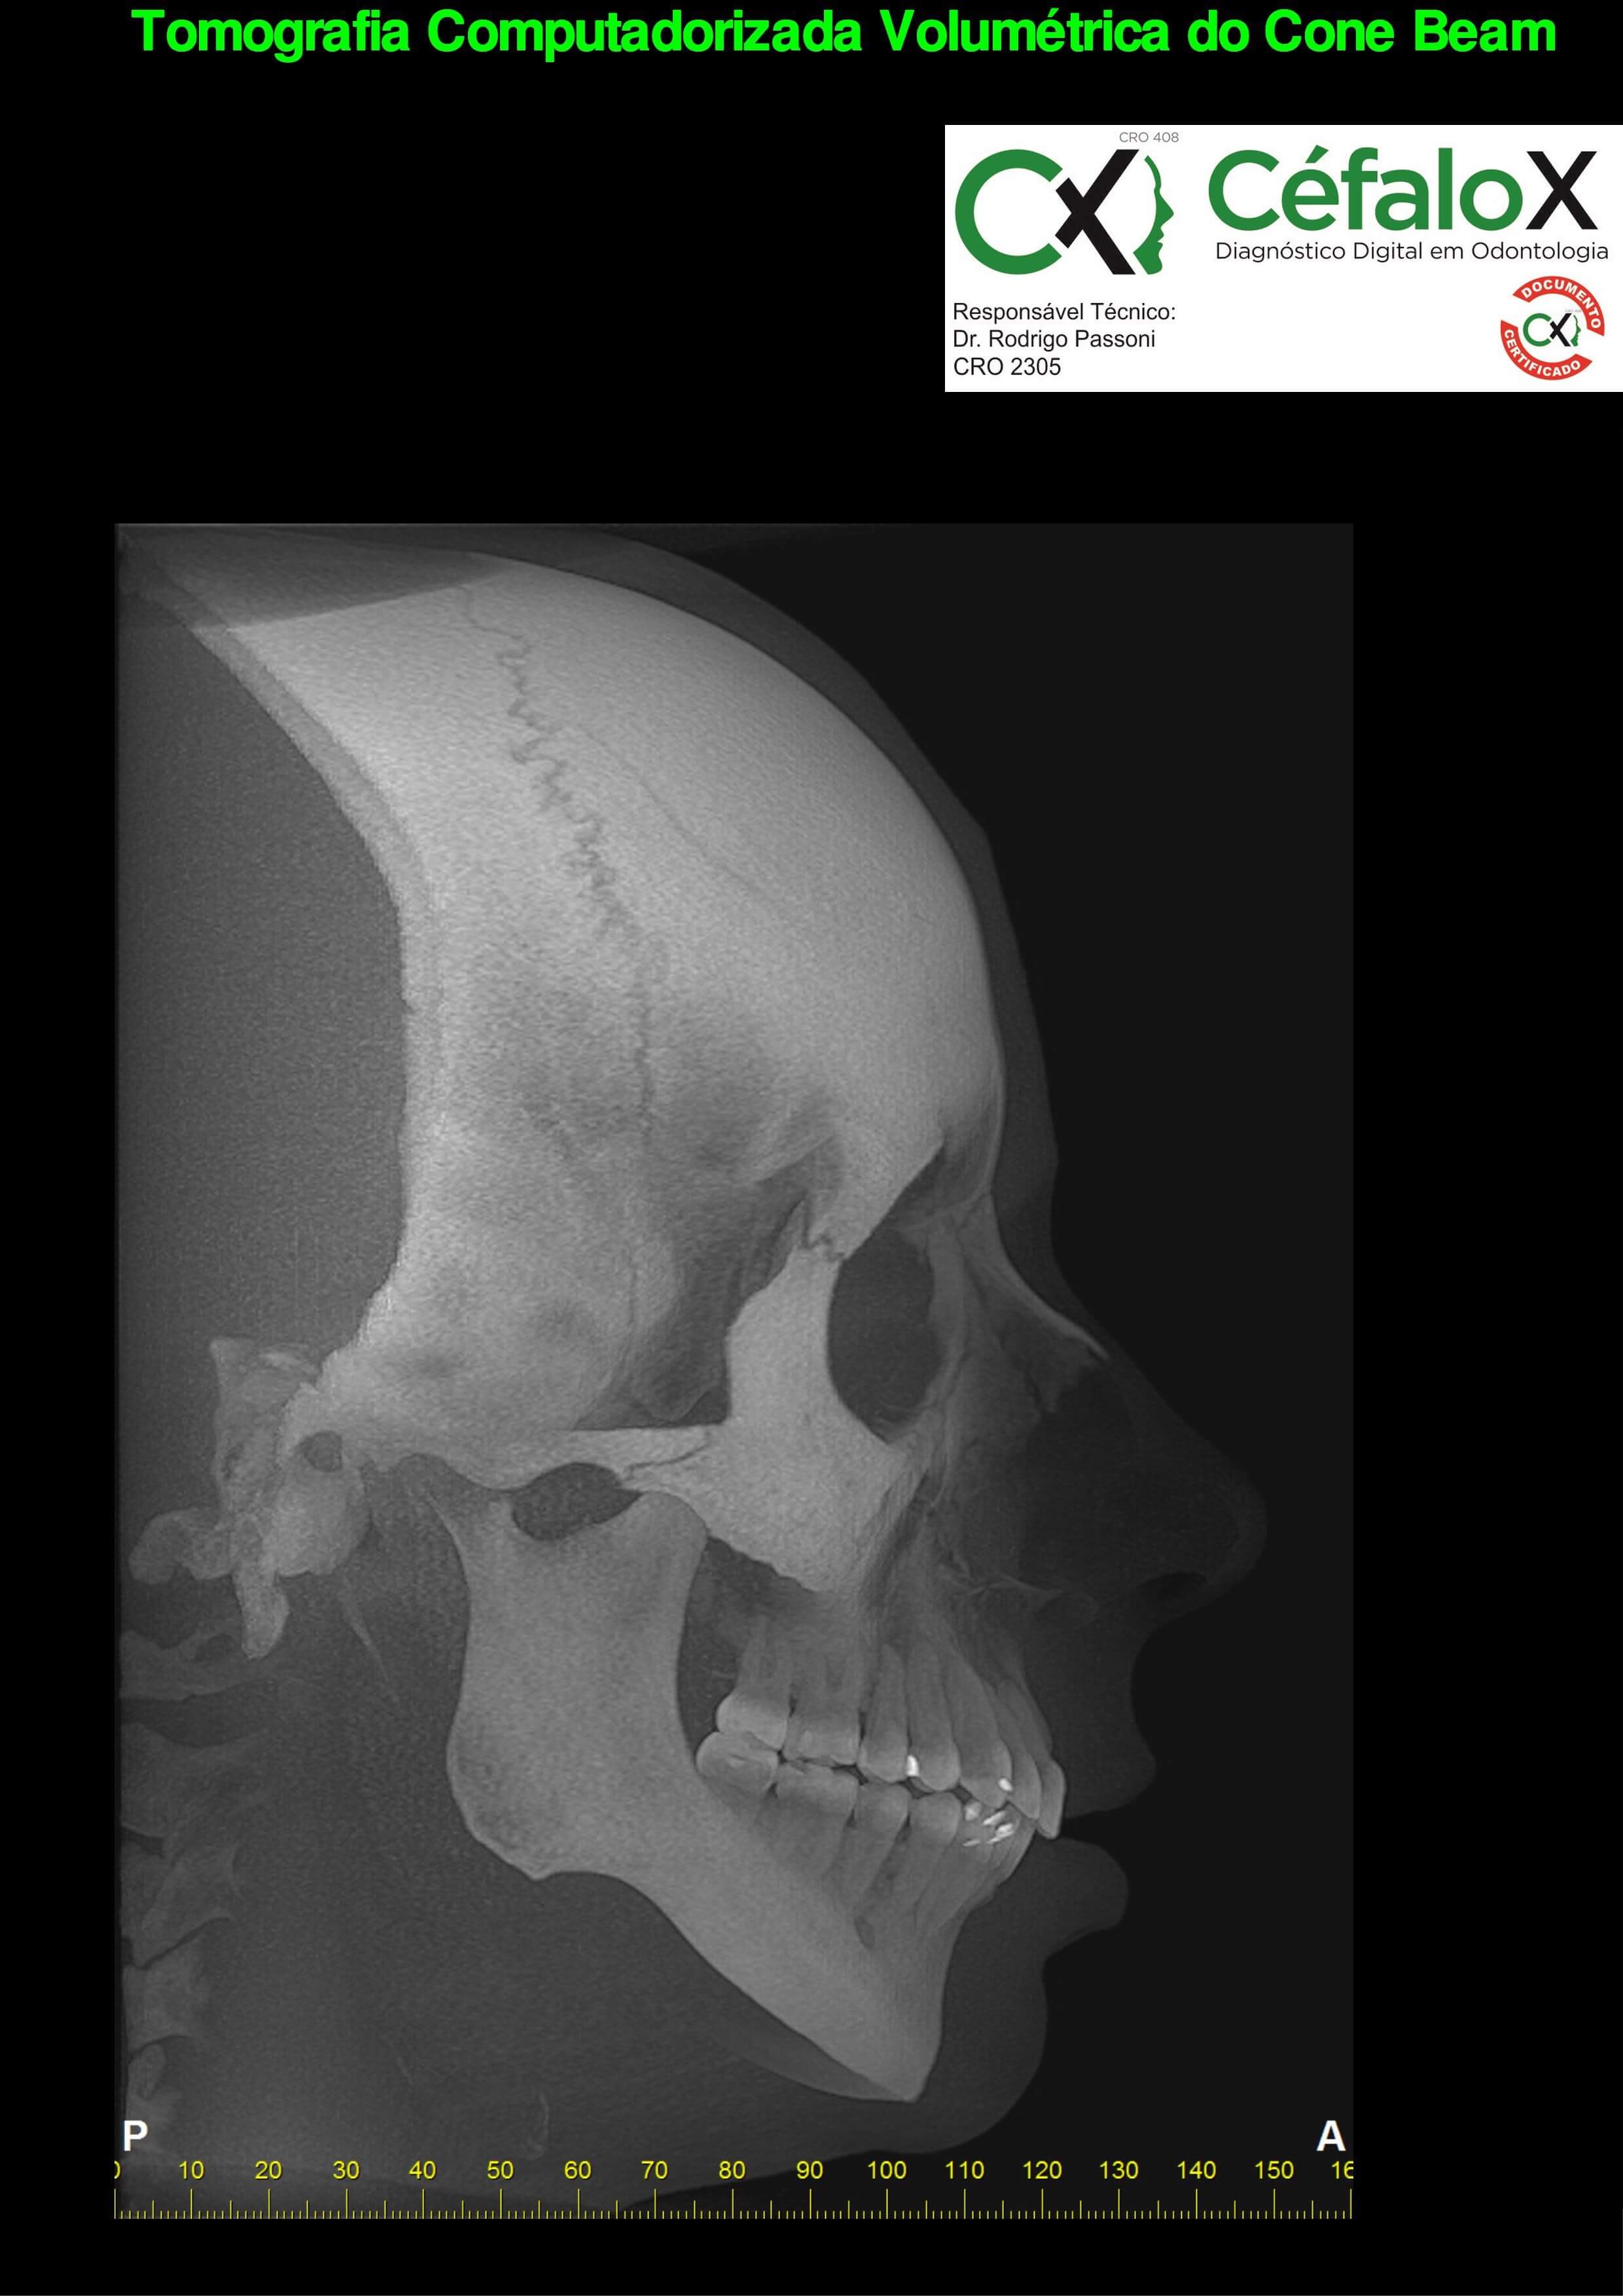

TC de face (do Hióide à Glabela), reconstrução 3D do tecido ósseo, radiografia panorâmica, telerradiografia lateral com traçado, cortes transversais e axial de maxila e mandíbula e arquivo DICOM- entregue em pasta de Pvc.

TC de face (do Hióide à Glabela), reconstrução 3D do tecido ósseo, radiografia panorâmica, telerradiografia lateral e frontal com traçado, cortes transversais e axial de maxila/mandíbula e arquivo DICOM – entregue em pasta de Pvc.

TC de face (do Hióide à Glabela), reconstruções 3D do tecido mole/ósseo/vias aéreas, radiografia panorâmica, telerradiografia lateral e frontal com traçado, cortes transversais e axial de maxila/mandíbula, ATM e arquivo DICOM – entregue em pasta e caixa de Pvc.